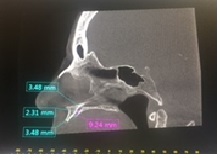

La primera medida perpendicular se obtuvo en el corte sagital oblicuo a nivel inferior del CNP situado desde la cortical interna hasta la cortical externa de su pared anterior. La segunda medida se obtuvo a nivel medio del mencionado conducto, equidistante entre la porción superior e inferior, situado desde la cortical interna y externa. La tercera medida se obtuvo a nivel superior de la pared anterior del CNP, a nivel del piso de fosas nasales y de cortical interna a cortical externa. La medida vertical se realizó desde la medida superior a la inferior horizontal en el centro de la luz del conducto (ver imagen 1 y 3). La medida transversal se obtuvo en un corte axial a nivel de un punto equidistante entre superior e inferior (ver imagen 2 y 4).

Se observa la medida del diámetro transversal del CNP

fotografía autores

fotografía autoresResultados

En los pacientes dentados el promedio del diámetro a nivel inferior es de 2,5mm, a nivel medio es de 1,75mm y superior es de 2,33mm. El promedio de la altura es de 10,68mm y el diámetro transversal es de 3,45mm (Tabla 1 y Gráfico 1). En los pacientes edéntulos el promedio del diámetro a nivel inferior es de 3,55mm, a nivel medio es de 2,55mm y superior es de 3,01mm. El promedio de la altura es de 7,9mm y el diámetro transversal es de 4,55mm (Tabla 2 y Gráfico 2).